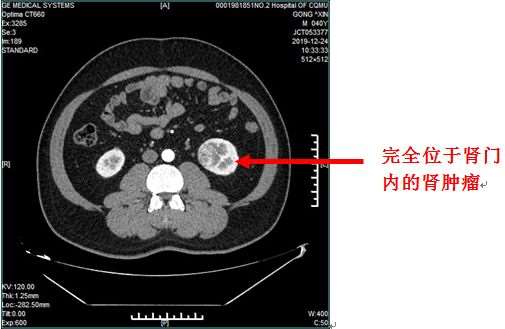

近日我院泌尿外科利用全息三维影像重建技术成功完成一例肾血管变异的复杂肾门内生型肿瘤剜除术。患者因体检于外院发现肾肿瘤,因肿瘤位于肾门,紧邻肾门内密集的大血管及肾盂输尿管。患者体重190斤,保肾意愿强烈,辗转我市多家大医院,均因手术难度高、风险大,不愿意为其手术治疗,遂来到重医附二院泌尿外科就诊。

刘川教授和胡自力教授通过仔细阅读患者影像学资料,发现患者肾脏肿瘤是一个内生型的肿瘤,而且位于肾脏的核心部位——肾门部。

对该部位实施保留肾脏的肿瘤剜除术难度极高,因为稍有不慎就有可能损伤血管造成大出血,或者破坏肾脏的集合系统,造成尿液外渗。内生性肿瘤从外观上看肾脏形态完全正常,无法看到其内部的肿瘤,可能在手术时,外科医生无法分辨肿瘤与正常组织,导致手术无从下手或者手术过程中肿瘤切除不干净。另外,患者体重较重,达到190斤,也增加了手术的难度,因为过量的肾周脂肪与肾包膜严重粘连会导致肾肿瘤边界不清、暴露困难,粘连严重的脂肪组织血供丰富,容易发生出血。此外患者CTA提示患者肾动脉血管变异较大,有三支动脉供血,且三支肾动脉包绕肾静脉,这无疑又增加了手术的难度。患者在来我院之前,曾辗转于多家大型医疗单位,医生提供的方案都是开放性肾脏探查或者直接的肾脏切除治疗方案。由于患者年龄不大,巨大的手术创伤和器官丢失都是患者和家属无法接受的,因此他们慕名找到泌尿外科刘川教授和胡自力教授。